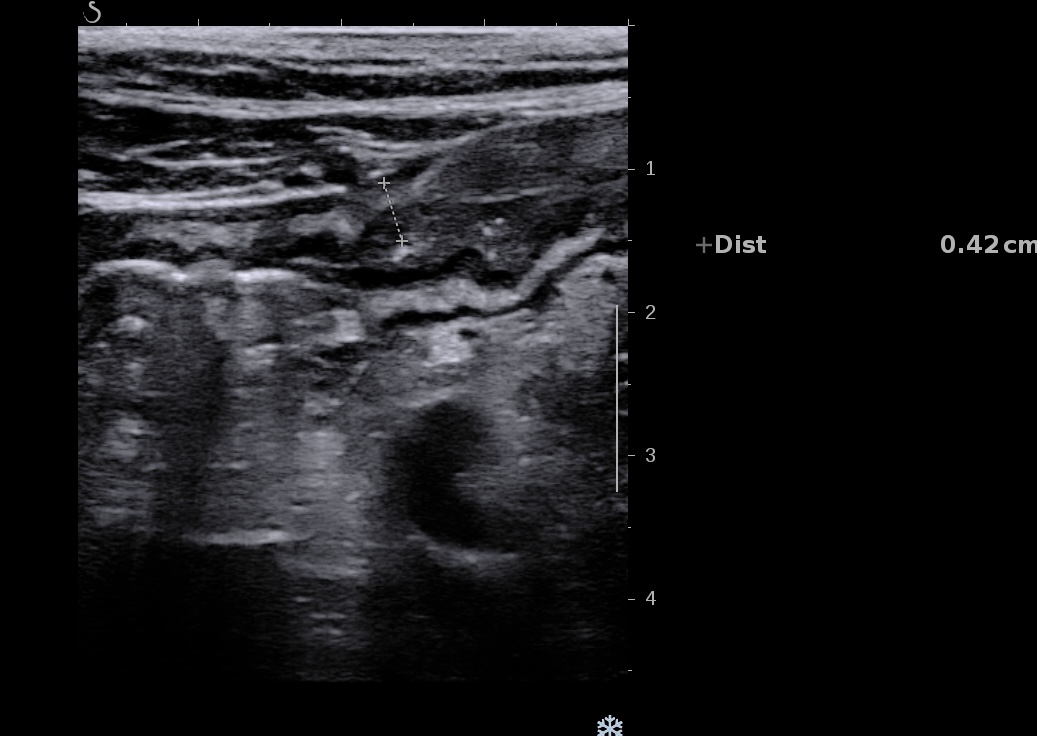

Epaississement entre 4.5 et 7 mm selon les segment, la structure en couche disparait totalement par endroit, à d’autre elle est partiellement conservée. Activité doppler intense de la paroi

Le Score de Milan (MUC) est à (1,4 x7+2) = 11,8